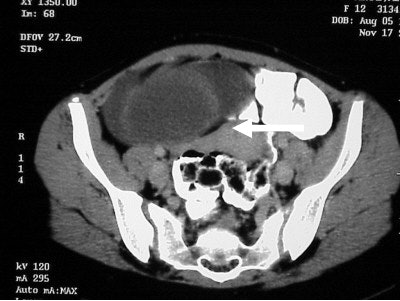

The image (Figure TC 2) demonstrates a contrast-filled bowel, the tip of the liver on the right, and a soft-tissue mass appearing at the level of the kidneys in the anterior portion of the abdomen.

In figure TC 3 we can see a large soft-tissue mass measuring approximately 9 cm wide by 6 cm in AP diameter, and 14 cm in height. It contains both fluid and semi-solid components of soft tissue as well as assorted calcifications. The mass appears to terminate (Figure TC 4) just above the level of the uterus (arrow).